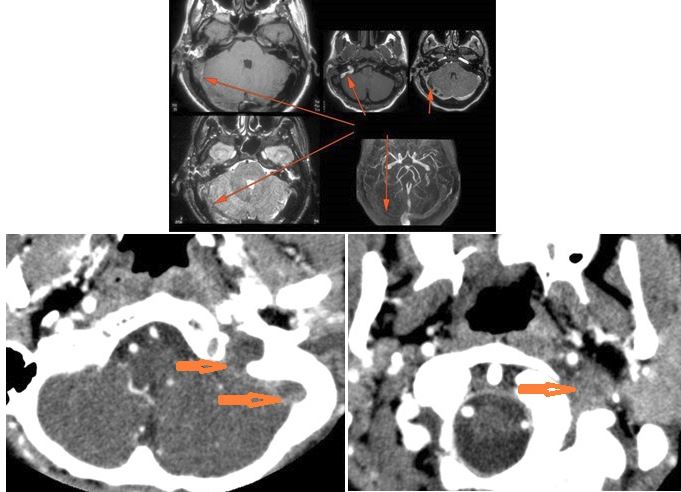

There is dural reactive or leptomeningeal enhancement involving the internal auditory canal and the 7th and 8th cranial nerves. [Yes/No]

There is likely meningitis involving the inferior temporal lobe or adjacent cerebellum or more remote meningeal sites. [Yes/No]

There is brain edema and/or evolving abscess present or, specifically, involving the inferior temporal lobe or adjacent cerebellum. [Yes/No]

There is evidence of thrombosis, thrombophlebitis or other occlusive or inflammatory process of the sigmoid sinus, transverse sinus, the vein of Labbe’ or jugular bulb or vein. [Yes/No]

There is inflammation of the distal internal carotid artery. [Yes/No]